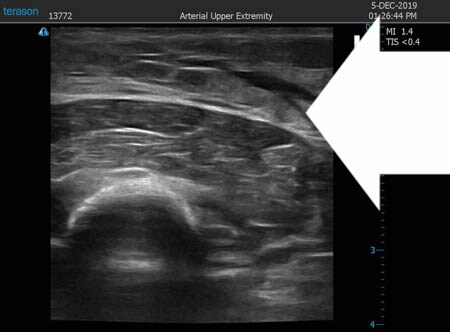

同様に左二の腕 ↓ ↓ ↓

↓ ↓ ↓